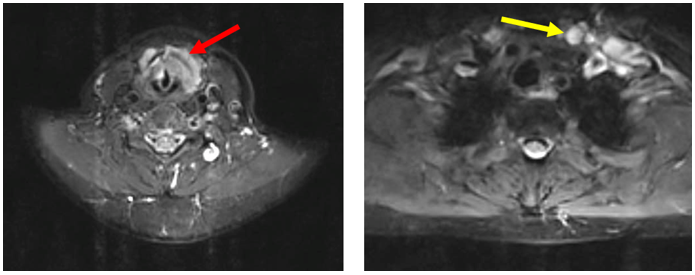

3.     Biến đổi trên chẩn đoán hình ảnh (trước và sau điều trị)

Hình ảnh MRI cổ: Hình ảnh tổn thương vùng hạ họng thanh quản giảm kích thước sau điều trị 3 tháng, từ 41 x 22mm (mũi tên đỏ) xuống còn kích thước 20 x 13mm (mũi tên xanh).

Hình ảnh MRI cổ: Hình hạch thượng đòn trái giảm kích thước sau 3 tháng điều trị, từ đường kính 10 mm (mũi tên đỏ) xuống còn 7mm (mũi tên vàng).

-         Sau 3 tháng, khối u hạ họng - thanh quản giảm kích thước còn 20 x 13mm, bệnh nhân cải thiện triệu chứng lâm sàng.